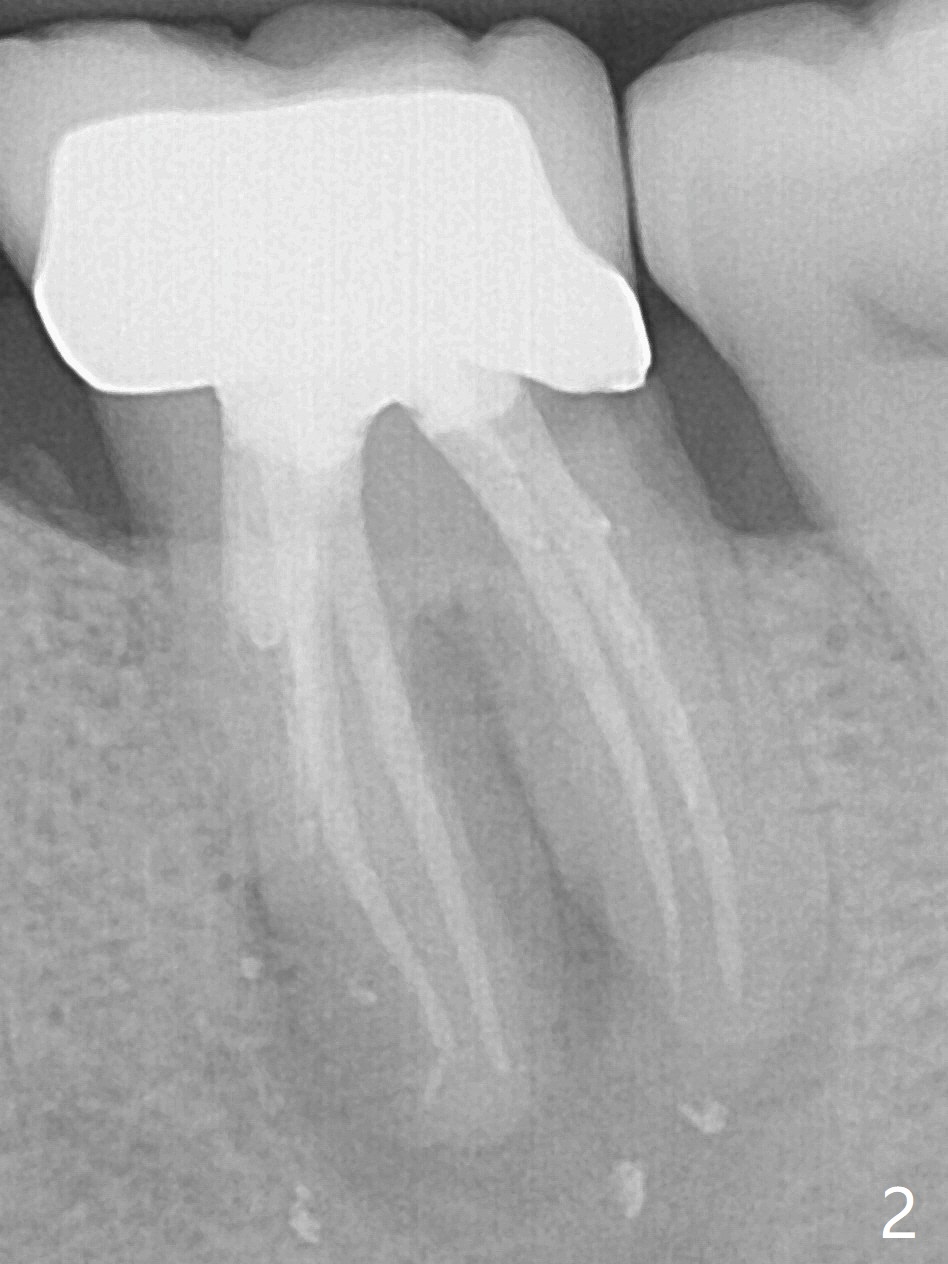

Extraction of the tooth #19 with large PARL (Fig.1,2) confirms the loss of buccal plate, but the crestal bone exists. After failure to place an implant in the middle socket with removal of the lingual septal bone, socket preservation is done with PRF and sticky bone (Fig.3). There is possibility to place a ~4 mm implant in the mesial socket (Fig.4). Or just drop a 5x11 mm Bicon Implant into the large socket, surrounded by sticky bone. When periodontal dressing is removed 18 days postop, the bone graft seems to remain to be "sticky" yellowish, while the granulation tissue has started to grow into the center of the socket from the previously buccal and lingual furcae (Fig.5 reddish). Granulation tissue seems to cover the bone graft (Fig.6), although there is smells when the periodontal dressing is removed. Bone height reduces nearly 3 months postop (Fig.7). The buccal plate collapses (Fig.8), but there seems no further bone loss 4 months postop (Fig.9). Because of buccal plate loss, an implant will be placed lingually with guide (Fig.10-12 green). Bone graft may be placed buccally after implant placement with probing.